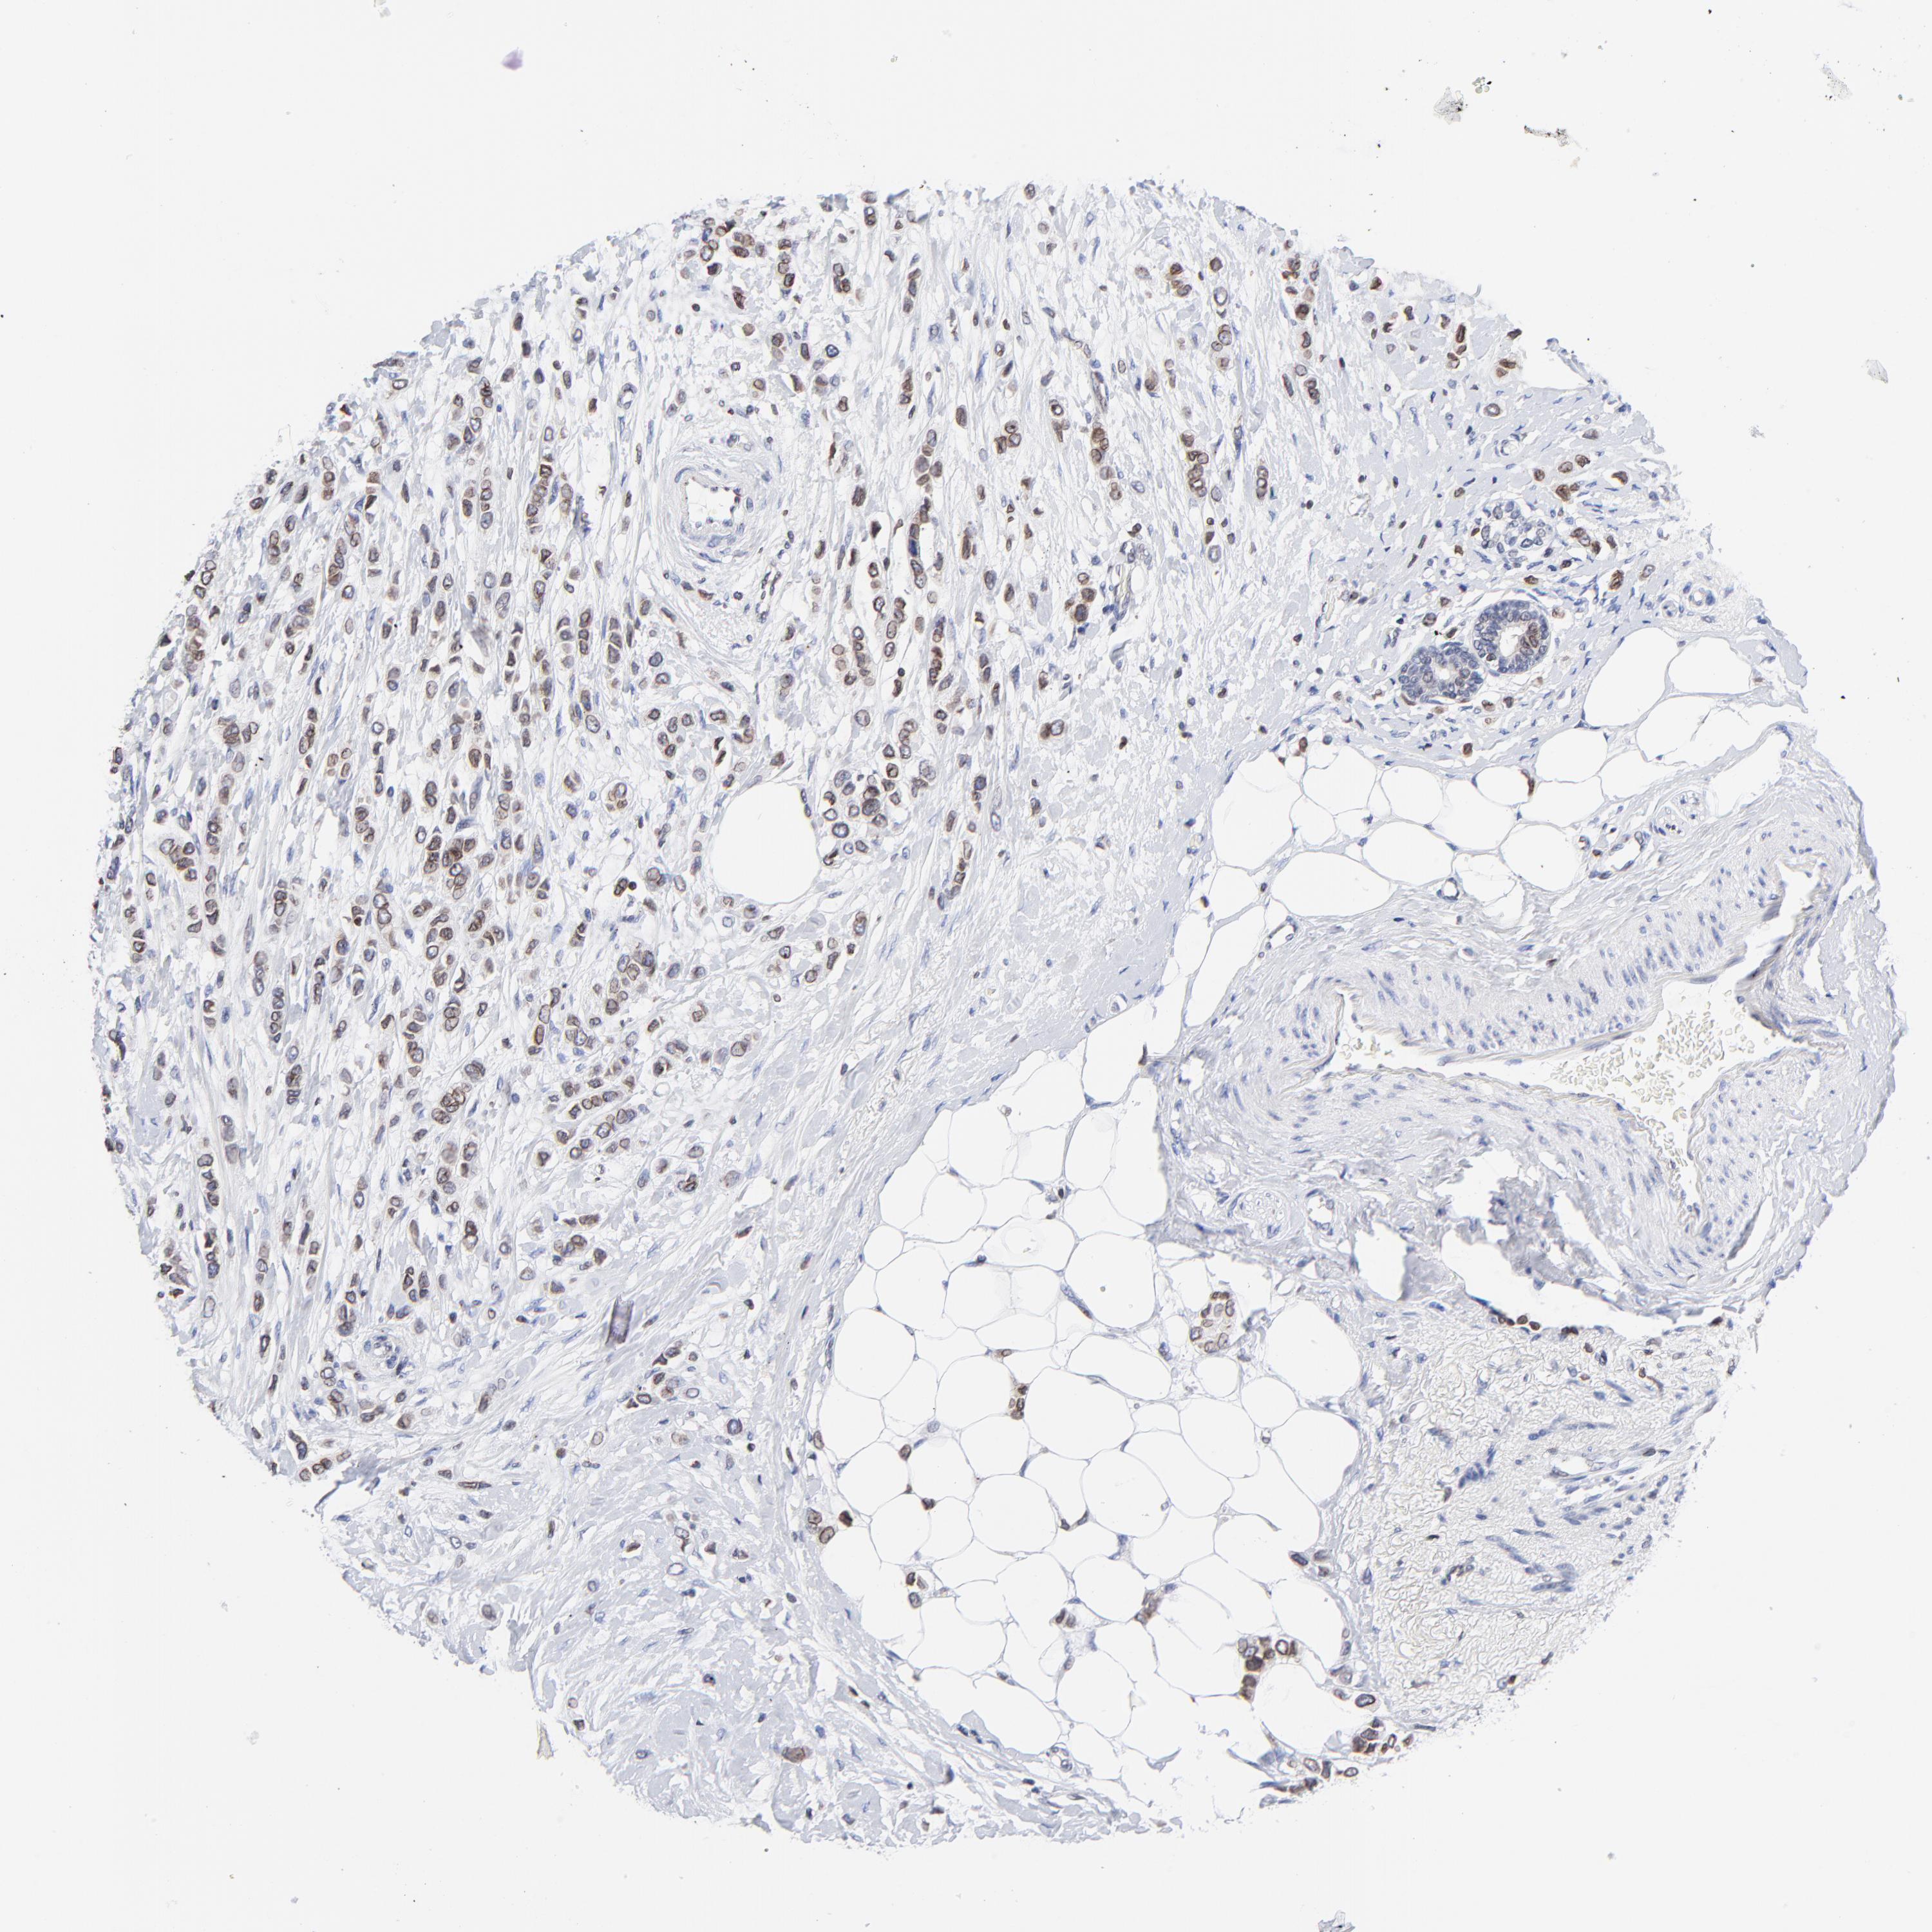

BRCA TCGA BRCA VALIDATION PROTEIN EXPRESSION

ANTIBODIES

AND

VALIDATION